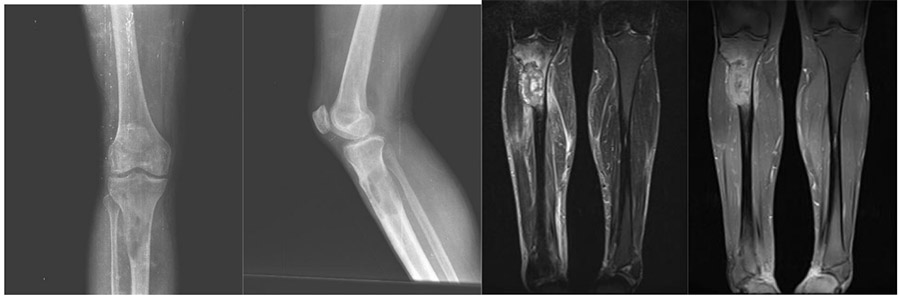

CASE 50: Laryngeal (Esophageal) cancer metastasis to the tibia

Before the surgery: X-ray shows bone destruction and risk of fracture due to metastasis at the upper end of the tibia, and MRI shows the tumor extending outside the bone and widespread edema.